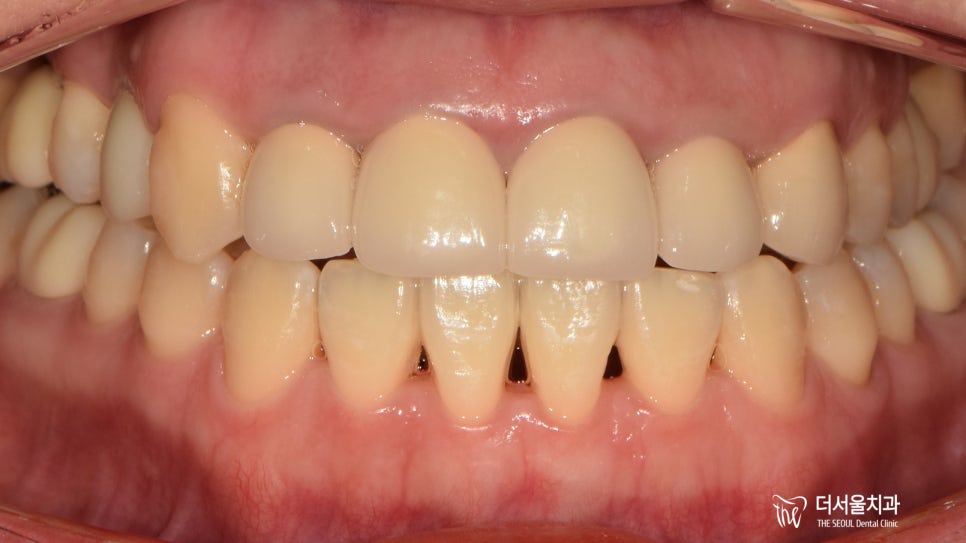

『초진』

툭 튀어나온듯한 입매와 다수의 치아 상실,

이 두 가지 문제가 관찰되었습니다.

이외에도 벌어진 앞니를 비롯하여

여기저기 상태가 좋지 않은 치아들이

구강 곳곳에 자리를 잡고 있었는데요.

앞니를 비롯하여 치료를 받았던 치아들이

꽤 많이 있는 것을 알 수 있었습니다.

이전과는 달리 딱 봐도 고른 치열이 눈에 띕니다.

가지런한 치아와 상실된 기능 회복으로

만족, 대만족을 하셨던 환자분^__^